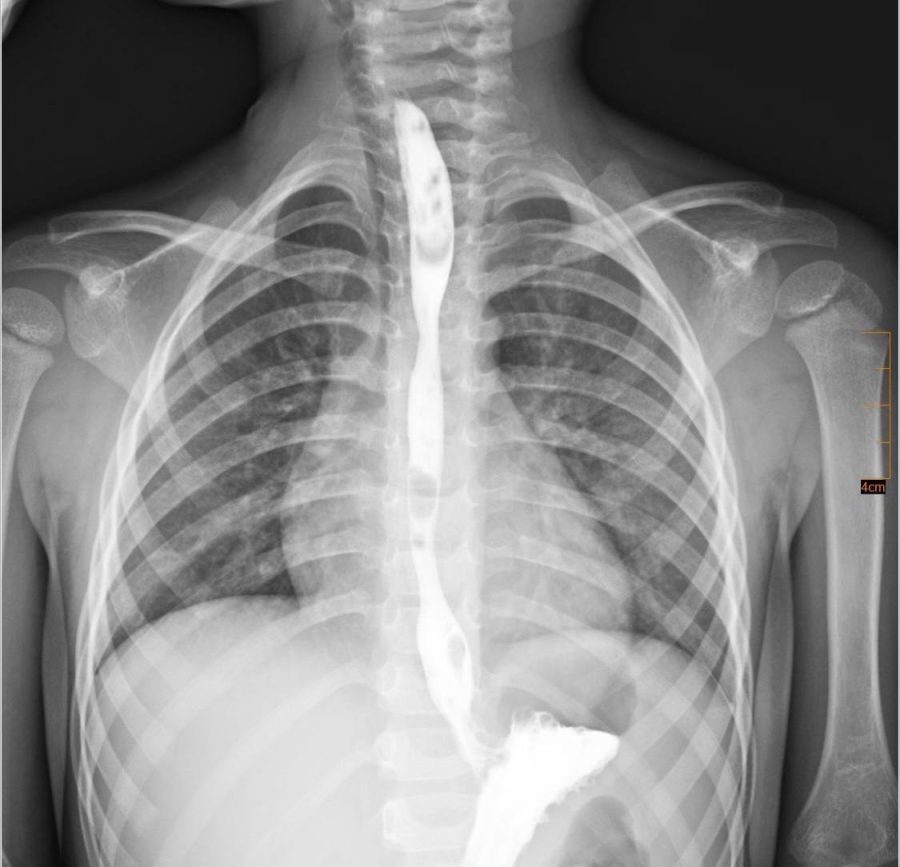

Рентген стравоходу з контрастною речовиною після одужання дитини. Фото: Центр дитячої медицини

Згодом у хлопчика сформувався критичний стеноз стравоходу – сильне звуження, через яке неможливо було їсти.

Лікарі вирішили проводити серію балонних дилатацій стравоходу – малоінвазивних ендоскопічних втручань, під час яких звужену ділянку поступово розширюють спеціальним балоном без виконання розрізів.